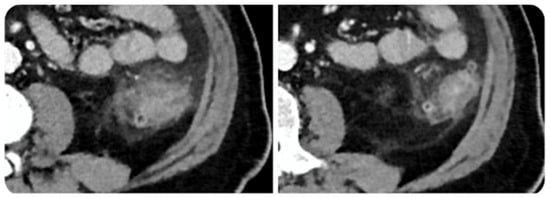

6.5. Pancreas